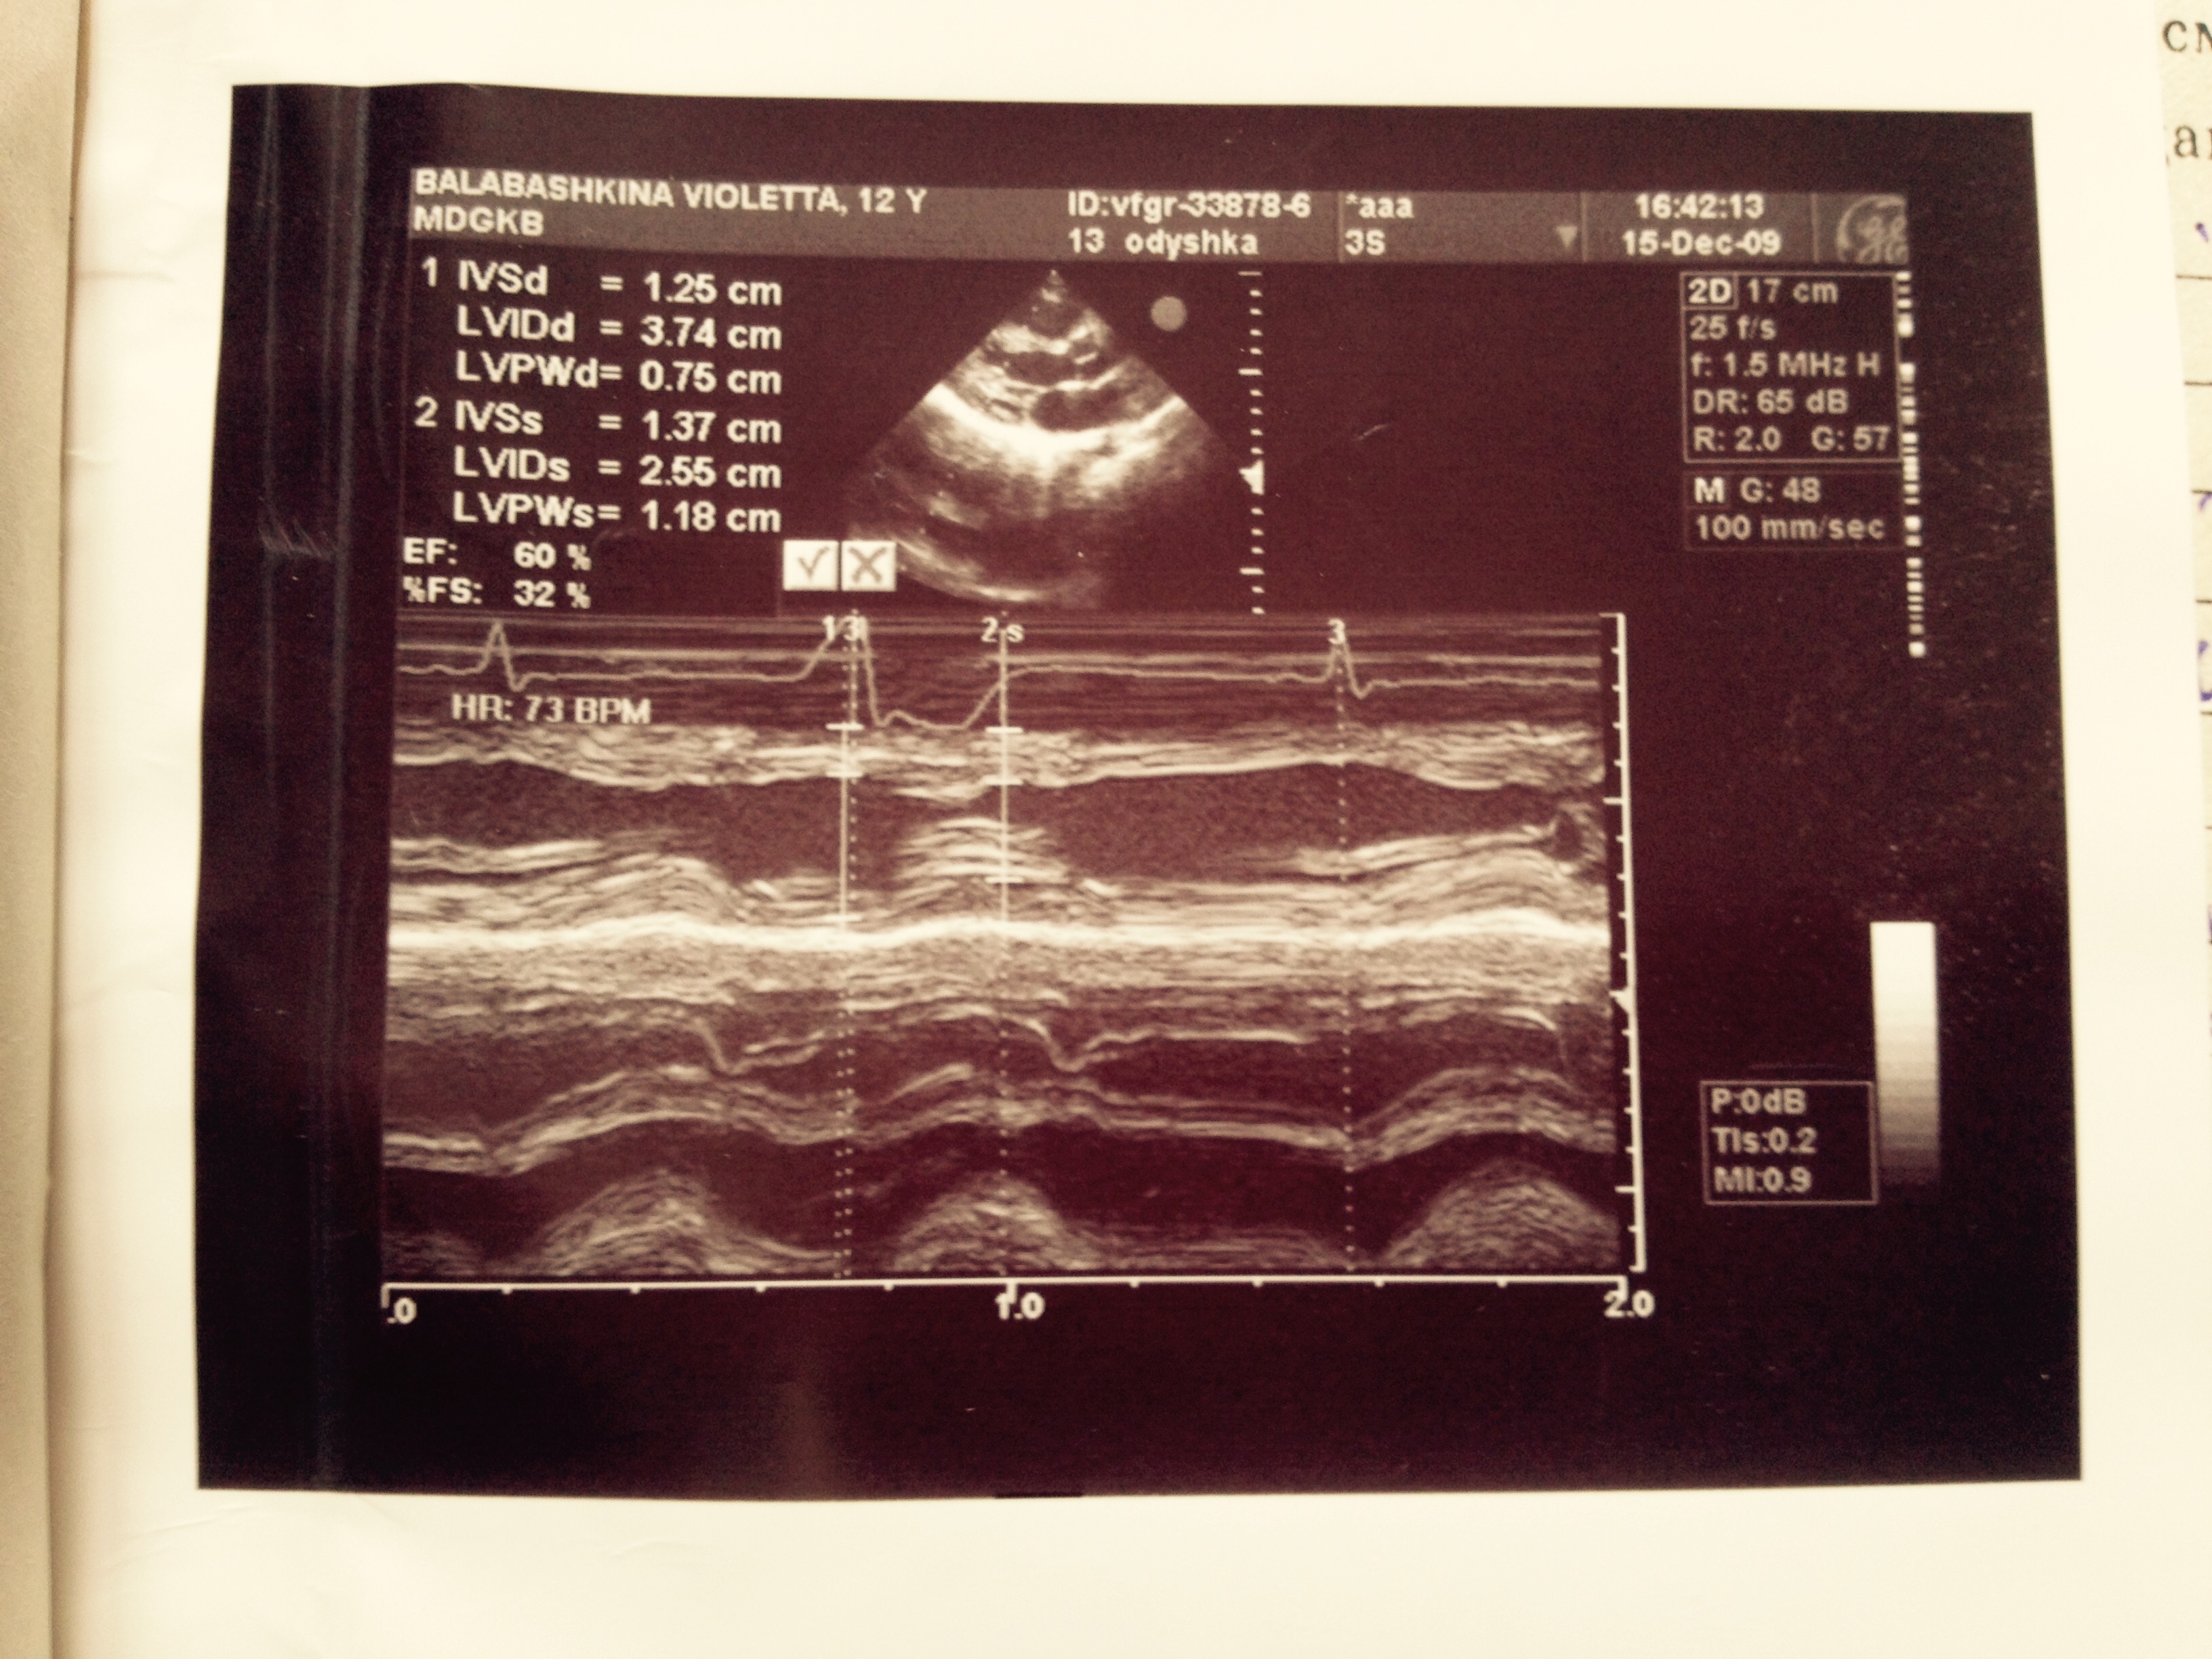

При подробном сборе анамнеза у мамы и, главное, разговоре с девочкой было выяснено, что накануне госпитализации в Измайловскую больницу на фоне психотравмирующего фактора (ссора с подругой) пациентка приняла большое количество таблеток аспирина (количество точно не помнит, более 10). Именно после этого появились выраженные вялость, шум в ушах, многократная рвота (от родителей скрыла), затруднения дыхания, с которыми пациентка была госпитализирована в Измайловскую больницу. При клинико-лабораторном наблюдении в Морозовской больнице — состояние средней тяжести, дыхательная недостаточность 1-й степени, клинико-лабораторных данных за манифестный СД не выявлено (гликированный гемоглобин 5,4%, гликемия в динамике от 3 до 6,7 ммоль/л, кетонемия — отрицательна, аглюкозурия), общий анализ крови — без патологии. Обращали на себя внимание тахипноэ до 36 в минуту, тахикардия до 90—100 в минуту, легкая смешанная одышка при нагрузке в отсутствие нарушений в биохимии крови, в том числе электролитных, выраженный систолический шум на верхушке в отсутствие изменений на ЭКГ. При УЗИ сердца выявлены редкие экстрасистолы со снижением гемодинамической эффективности. Заключение невролога: мелкоразмашистый горизонтальный и вертикальный нистагм.

1. УЗИ сердца пациентки | |